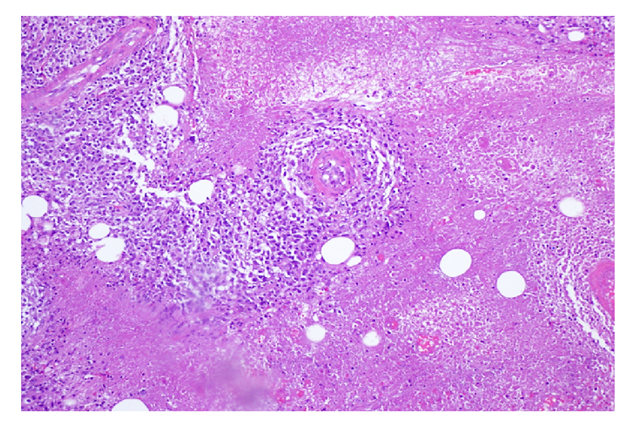

Figure 1 H&E stain of a lymph node section demonstrating angiocentric infiltration of large atypical lymphocytes with prominent nuclei and extensive necrosis.